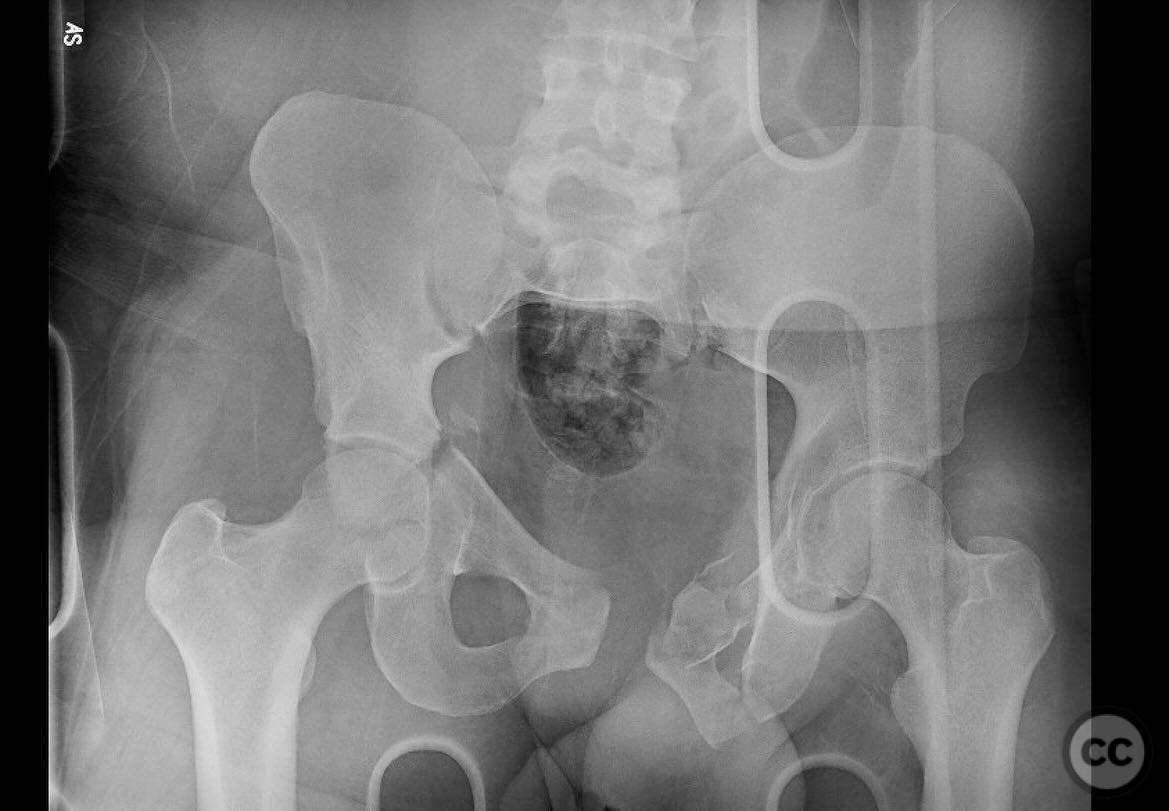

Combined Pelvic Ring and Transverse Acetabulum Fracture with Bladder Injury

Clinical and radiological findings:  The patient presented with a highly unstable pelvic ring injury and a transverse acetabulum fracture, accompanied by a bladder injury. The bladder injury was addressed emergently with a low vertical midline Pfannenstiel incision for repair, followed by the placement of a low right-sided suprapubic catheter. Radiological imaging confirmed the transverse acetabular fracture and disruption of the left sacroiliac joint, along with a displaced sacral fracture.